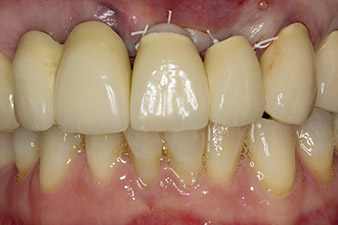

Une fois la cicatrisation primaire obtenue, les tissus mous ont été formés à l'aide du bridge doublé à la base. Deux mois plus tard, la zone a été exposée au moyen d'une incision de la crête alvéolaire légèrement orientée côté palatin (Fig 2). Les dimensions de l'os alvéolaire se sont avérées suffisantes en position 22. Les Figures 2 et 4 illustrent la préparation du lit implantaire, le taraudage et la pose de l'implant à l'aide de l'Implantmed.

Afin de compenser la perte osseuse parodontale et d'obtenir un résultat esthétiquement satisfaisant, la pose de l'implant a été associée à une régénération osseuse guidée (GBR) avec matériau de substitution xénogénique et membrane collagène. (Fig. 5 et 6).